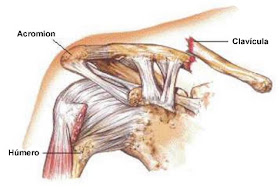

Aunque no es de las lesiones más frecuentes en el jugador de campo (si en el portero), vamos a hablar de la fractura de clavícula, ya que aproximadamente el 5% de todas las fracturas tratadas en las urgencias de los hospitales tiene a la clavícula como protagonista. Que la clavícula se fracture, aunque sea de forma indirecta, es debido a un duro impacto tras extender la mano durante una caída o bien por una caída sobre el propio hombro.La clavícula es el hueso largo que une la parte superior del brazo con el tronco del cuerpo: un extremo de la clavícula se une con el esternón y el otro extremo con el omoplato. La clavícula, cuya parte más frágil es la unión entre sus dos tercios medio y lateral, forma la única articulación que une la cintura escapular con el tronco y protege importantes vasos sanguíneos, el pulmón y el plexo braquial. Las fracturas de la clavícula que terminan desplazadas de su posición anatómica pueden lesionar estas estructuras debido a su proximidad y lo afilado que resultan los bordes astillados.